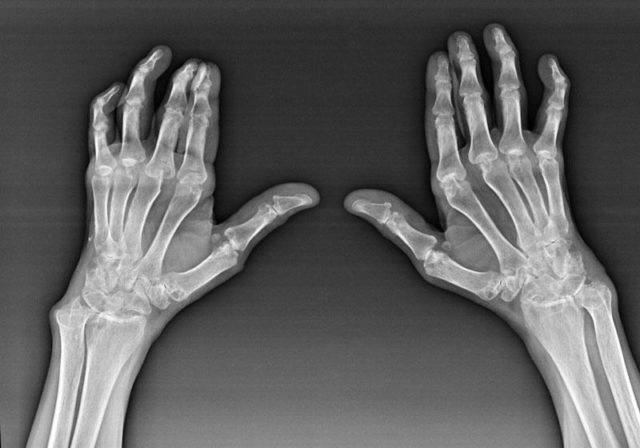

Для более точного определения характера повреждений сустава часто рекомендуется рентгенография. Этот метод помогает выявить изменения, такие как уменьшение толщины хрящевой ткани, сужение суставной щели и наличие остеофитов. Также для обнаружения даже незначительных изменений в структуре сустава могут быть назначены дополнительные исследования, такие как компьютерная томография (КТ) или магнитно-резонансная томография (МРТ).